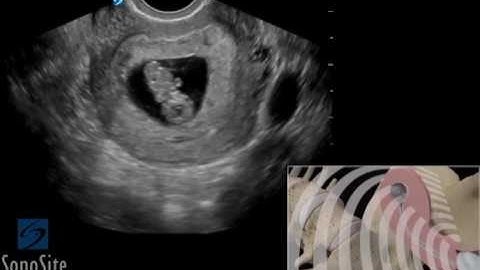

Lecture 4: Ectopic Pregnancy Free Fluid with Prof. Michael Bajka